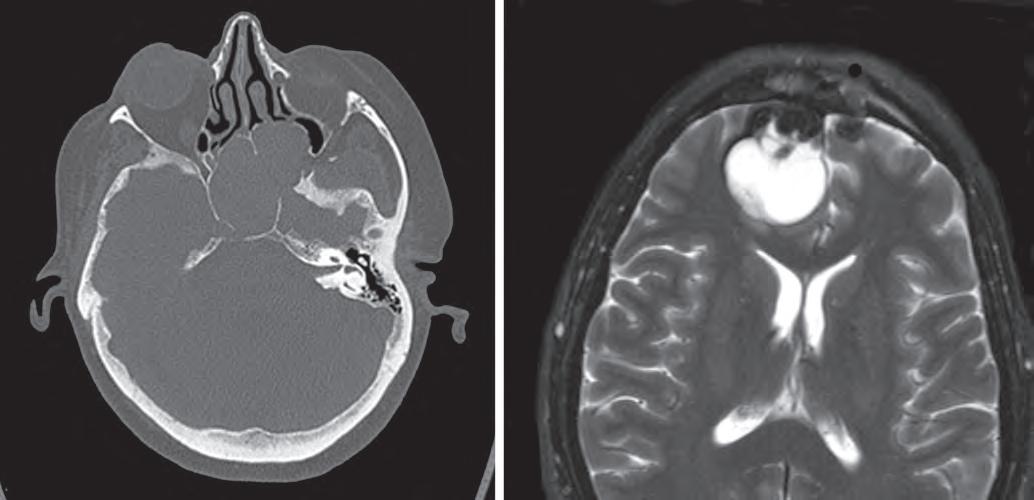

1.7

This computed tomography scan demonstrates a sphenoid sinus mucocele, with expansion of the sinus with secretions and thinning and remodeling of the surrounding bones (A). This T2-weighted magnetic resonance imaging scan shows a fluid-filled mucocele involving the brain (B).

of the orbit or cranial cavity (see Fig. 1.7B). Given these dramatic symptoms and radiographic features, a neoplastic process is often suspected clinically.